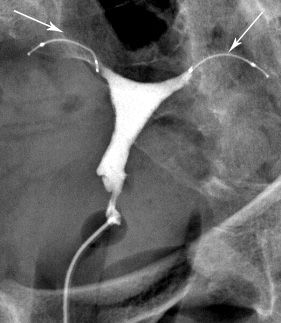

Hystérographie

Qu'est-ce que c'est ?

L’examen a pour but d’étudier la cavité utérine et la perméabilité des trompes.

Elle est réalisée par voie endovaginale après introduction d’un spéculum (comme lors d’un examen gynécologique).

Le produit opaque injecté rend visible sur les radiographies la cavité utérine et les trompes. Cet injection provoque une gène comparable à celle ressentie lors de règles douloureuses.

Les radiographies sont effectuées avant, pendant et après l’opacification.La préparation